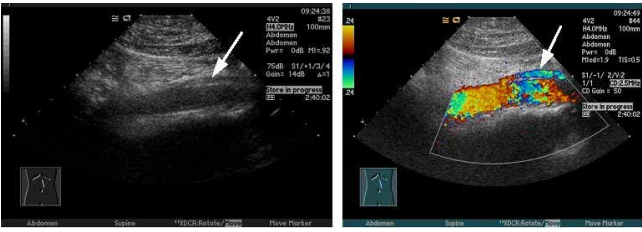

59 所附之超音波掃描圖為肚臍上方三公分處所做的縱切面掃描,箭號所指的構造最可能為:

(A)腎動脈 (B)腎靜脈 (C)上腸繫膜靜脈 (D)下腸繫膜動脈